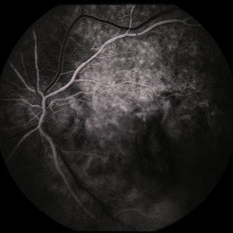

RPE Tear

RPE Tear

Sep 9 2014 by David Callanan, MD

78-year-old male, RPE tear.

Condition/keywords: retinal pigment epithelium